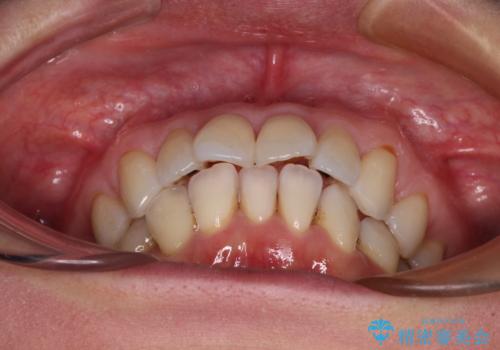

- 前方に飛び出した前歯を気にして来院された患者様です。

通常であれば上下左右の第一小臼歯4本を抜歯して口元の突出感を改善しますが、下顎前歯が1本欠損しており、上下の歯の数がアンバランスであるため、4本抜歯するかどうか悩むところでした。

上顎前歯はやや小さめで、下顎前歯はやや大きめであったため、上下左右4本を抜歯しても左右奥歯の咬み合わせは理想に近い状態を達成できると判断し、上下左右の第一小臼歯4本を抜歯し、ワイヤー装置にて矯正治療を行うこととしました。